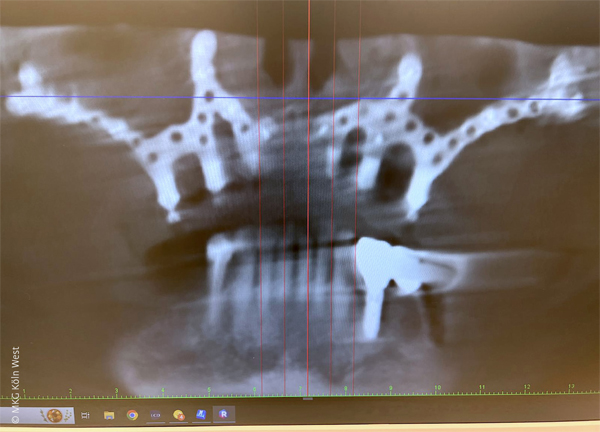

Anhand von zwei exemplarischen Patientenfällen aus der Praxis MKG Köln West werden das operative Vorgehen, die digitale Planungslogik sowie das klinische Ergebnis bei Verwendung eines patientenspezifischen subperiostalen Gerüstimplantats dargestellt. Beide Patientinnen wurden nach ausführlicher Aufklärung über konventionelle Alternativen letztlich mit einem individuell gefertigten Implantatsystem (IPS Implants® Preprosthetic, KLS Martin Group, Tuttlingen, Deutschland) im Oberkiefer versorgt. Die digitale Planung erfolgte interdisziplinär durch das Behandlerteam (Mund-Kiefer-Gesichtschirurg:in, Prothetiker:in) in Zusammenarbeit mit Ingenieur:innen der Herstellerfirma. Hierbei wurden die vorhandenen patientenspezifischen Daten – dreidimensionale Volumentomographie (DVT/CT) und intraorale Scan-Daten der Kiefer mit und ohne Prothese – gemeinsam ausgewertet, um ein ideales Implantatdesign nach dem Prinzip der Rückwärtsplanung („von der Prothese zum Knochen“) zu erstellen. Wesentliche Parameter wie vertikale Dimension (Bisshöhe) und Okklusalebene wurden vorab festgelegt. Die Geometrie des Kieferknochens wurde auf ausreichende Dicke und Dichte für die geplante Verschraubung/Osteosynthese geprüft und das virtuelle Gerüstdesign so angepasst, dass nach Einbringen des Implantats ein spannungsfreier Weichgewebsverschluss möglich ist. In die CAD-Planung wurden geführte Bohrschablonen integriert, welche die exakte Positionierung der Fixationsschrauben und – falls erforderlich – die partielle Reduktion prominenter knöcherner Strukturen (z. B. scharfe Alveolarkammanteile) vorgaben. So konnte das Implantatgerüst passgenau („maßgeschneidert“) auf den knöchernen Strukturen des Oberkiefers aufliegen. Die Herstellung des Gerüsts erfolgte mittels SLM als einteiliges (Fall 1) bzw. zweigeteiltes (Fall 2) Titanimplantat mit integrierten prothetischen Pfeilern. Zusätzlich zur Falldarstellung wurde eine Literaturrecherche aktueller Studien einschließlich systematischer Übersichtsarbeiten durchgeführt, um die klinischen Ergebnisse und Komplikationsraten moderner subperiostaler Implantate einordnen zu können.

Über einen oberen vestibulären Bogenschnitt mit hoher marginaler Inzision wurde der Oberkiefer flächig subperiostal dargestellt (Freilegung der Apertura piriformis, beider Jochbein- bzw. Crista zygomaticus-Regionen sowie des atrophierten Alveolarkamms). Anhand der CAD/CAM-Bohrschablone wurden die vorgesehenen osteosynthetischen Schraubenkanäle in den tragfähigen knöchernen Strukturen des Viszerokraniums präpariert.

Anschließend wurde das einteilige Titan-Implantatgerüst inseriert und mit 1,5 mm-Titanschrauben (KLS Martin) an insgesamt vier Fixationspunkten stabil am Oberkiefer verschraubt (unter anderem paramaxillär und im Jochbeinbereich). Zur Austrittssicherung der vier Implantatpfeiler durch die Schleimhaut wurden gezielt kleine Stichinzisionen in der fixierten Gingiva angelegt.

Die zweite Patientin (62 Jahre) wies ein parodontal stark geschädigtes Restgebiss im Oberkiefer auf. Nach Extraktion der nicht erhaltungswürdigen Zähne im Front- und Seitenzahnbereich war es intraoperativ zu einer ausgedehnten Mund-Antrum-Verbindung regio 16 (kommunizierende Kieferhöhle nach Zystektomie) gekommen. Die Patientin wünschte eine zeitnahe festsitzende Rehabilitation des Oberkiefers, wollte jedoch nach Möglichkeit keine vorgängigen Augmentationsverfahren durchlaufen. Nach ausführlicher Beratung über konventionelle augmentative Optionen (Sinuslift beidseits, umfangreiche laterale und vertikale Augmentation des Alveolarfortsatzes mit mehrmonatiger Heilungsdauer) entschied sich die Patientin für die Versorgung mit einem patientenspezifischen subperiostalen Implantat, das – analog zu Fall 1 – in Intubationsnarkose ambulant inseriert werden konnte. In diesem Fall wurde ein zweiteiliges Implantatgerüst für den zahnlosen Oberkiefer geplant, das insgesamt sechs Pfeiler für die prothetische Suprastruktur vorsah. Aufgrund der ausgeprägten Atrophie mit spitz auslaufendem Alveolarkamm war hier im Gegensatz zu Fall 1 zunächst eine gezielte Abtragung des Alveolarfortsatzes notwendig, um eine breitaufliegende, spannungsfreie Adaptation des Gerüsts zu ermöglichen. Die angefertigte Bohrschablone enthielt aus diesem Grund zusätzlich einen integrierten „Cutting Guide“ zur exakten Resektion der knöchernen Kammanteile in der Frontregion.

Nach erfolgter Alveolarkammglättung wurde jeweils rechts und links ein Implantatsegment passgenau aufgelegt und mit dem 1,5 mm MaxDrive-Schraubensystem fest am Knochen fixiert. Sechs transgingivale Pfeiler wurden durch entsprechende Stichinzisionen ausgeleitet und das Gerüst analog zu Fall 1 vestibulär mit verschobenem Bichat-Fettgewebe abgedeckt.